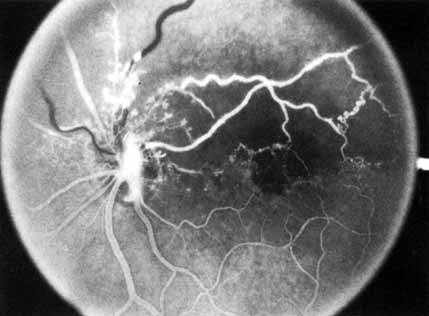

Fig. 5 Fluorescein angiogram of acute ischemic retinal vein occlusion. Capillary nonperfusion is essentially 100%.